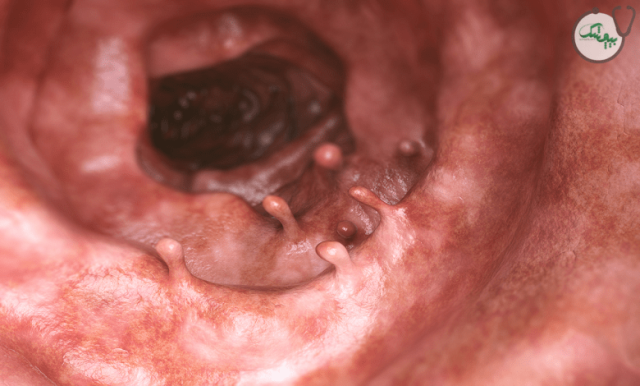

پولیپ های معده (پولیپ گاستریک)، توده‌ های کوچکی هستند که در پوشش داخلی معده ایجاد می‌ شوند. این پولیپ ها معمولاً به طور اتفاقی در طول آندوسکوپی تشخیص داده می شوند و در اغلب موارد خوش‌ خیم (غیرسرطانی) هستند، اما تعداد کمی از انواع آنها می‌ توانند به مرور زمان، پیش سرطانی یا سرطانی شوند.

تشخیص پولیپ معده معمولاً در طول آندوسکوپی فوقانی انجام می‌ شود، که در آن یک دوربین انعطاف‌ پذیر وارد معده می شود و امکان مشاهده پوشش معده و هرگونه پولیپ در آن را فراهم می‌ کند. متخصصان، پولیپ‌ ها را بر اساس اندازه، تعداد، شکل و محل قرارگیری ارزیابی می‌ کنند. همچنین در صورت مشاهده پولیپ در طی آندوسکوپی، از بافت آنها نمونه برداری می شود تا نوع پولیپ و خوش خیم، پیش سرطانی یا بد خیم بودن آنها مشخص شود. در اغلب موارد برای تشخیص و ارزیابی پولیپ های معده تصویربرداری استفاده نمی شود، مگر اینکه پولیپ بسیار بزرگ باشد.